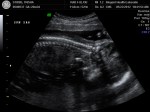

Today was ultrasound day!!!

Everything looked PERFECT. Baby is measuring in the 74th percentile, and 4 days ahead of my 10/07/12 due date– all fantastic news. To give you a perspective, Sam never measured above the 3rd percentile… ever. And Jack might have measured in the 5th percentile towards the end of the pregnancy? Oh, and they measured 3-4 weeks behind my 01/25/11 due date.

Heartbeat was 144. I’ve gained a few more pounds and am feeling great.

Here are pictures from the big appointment!